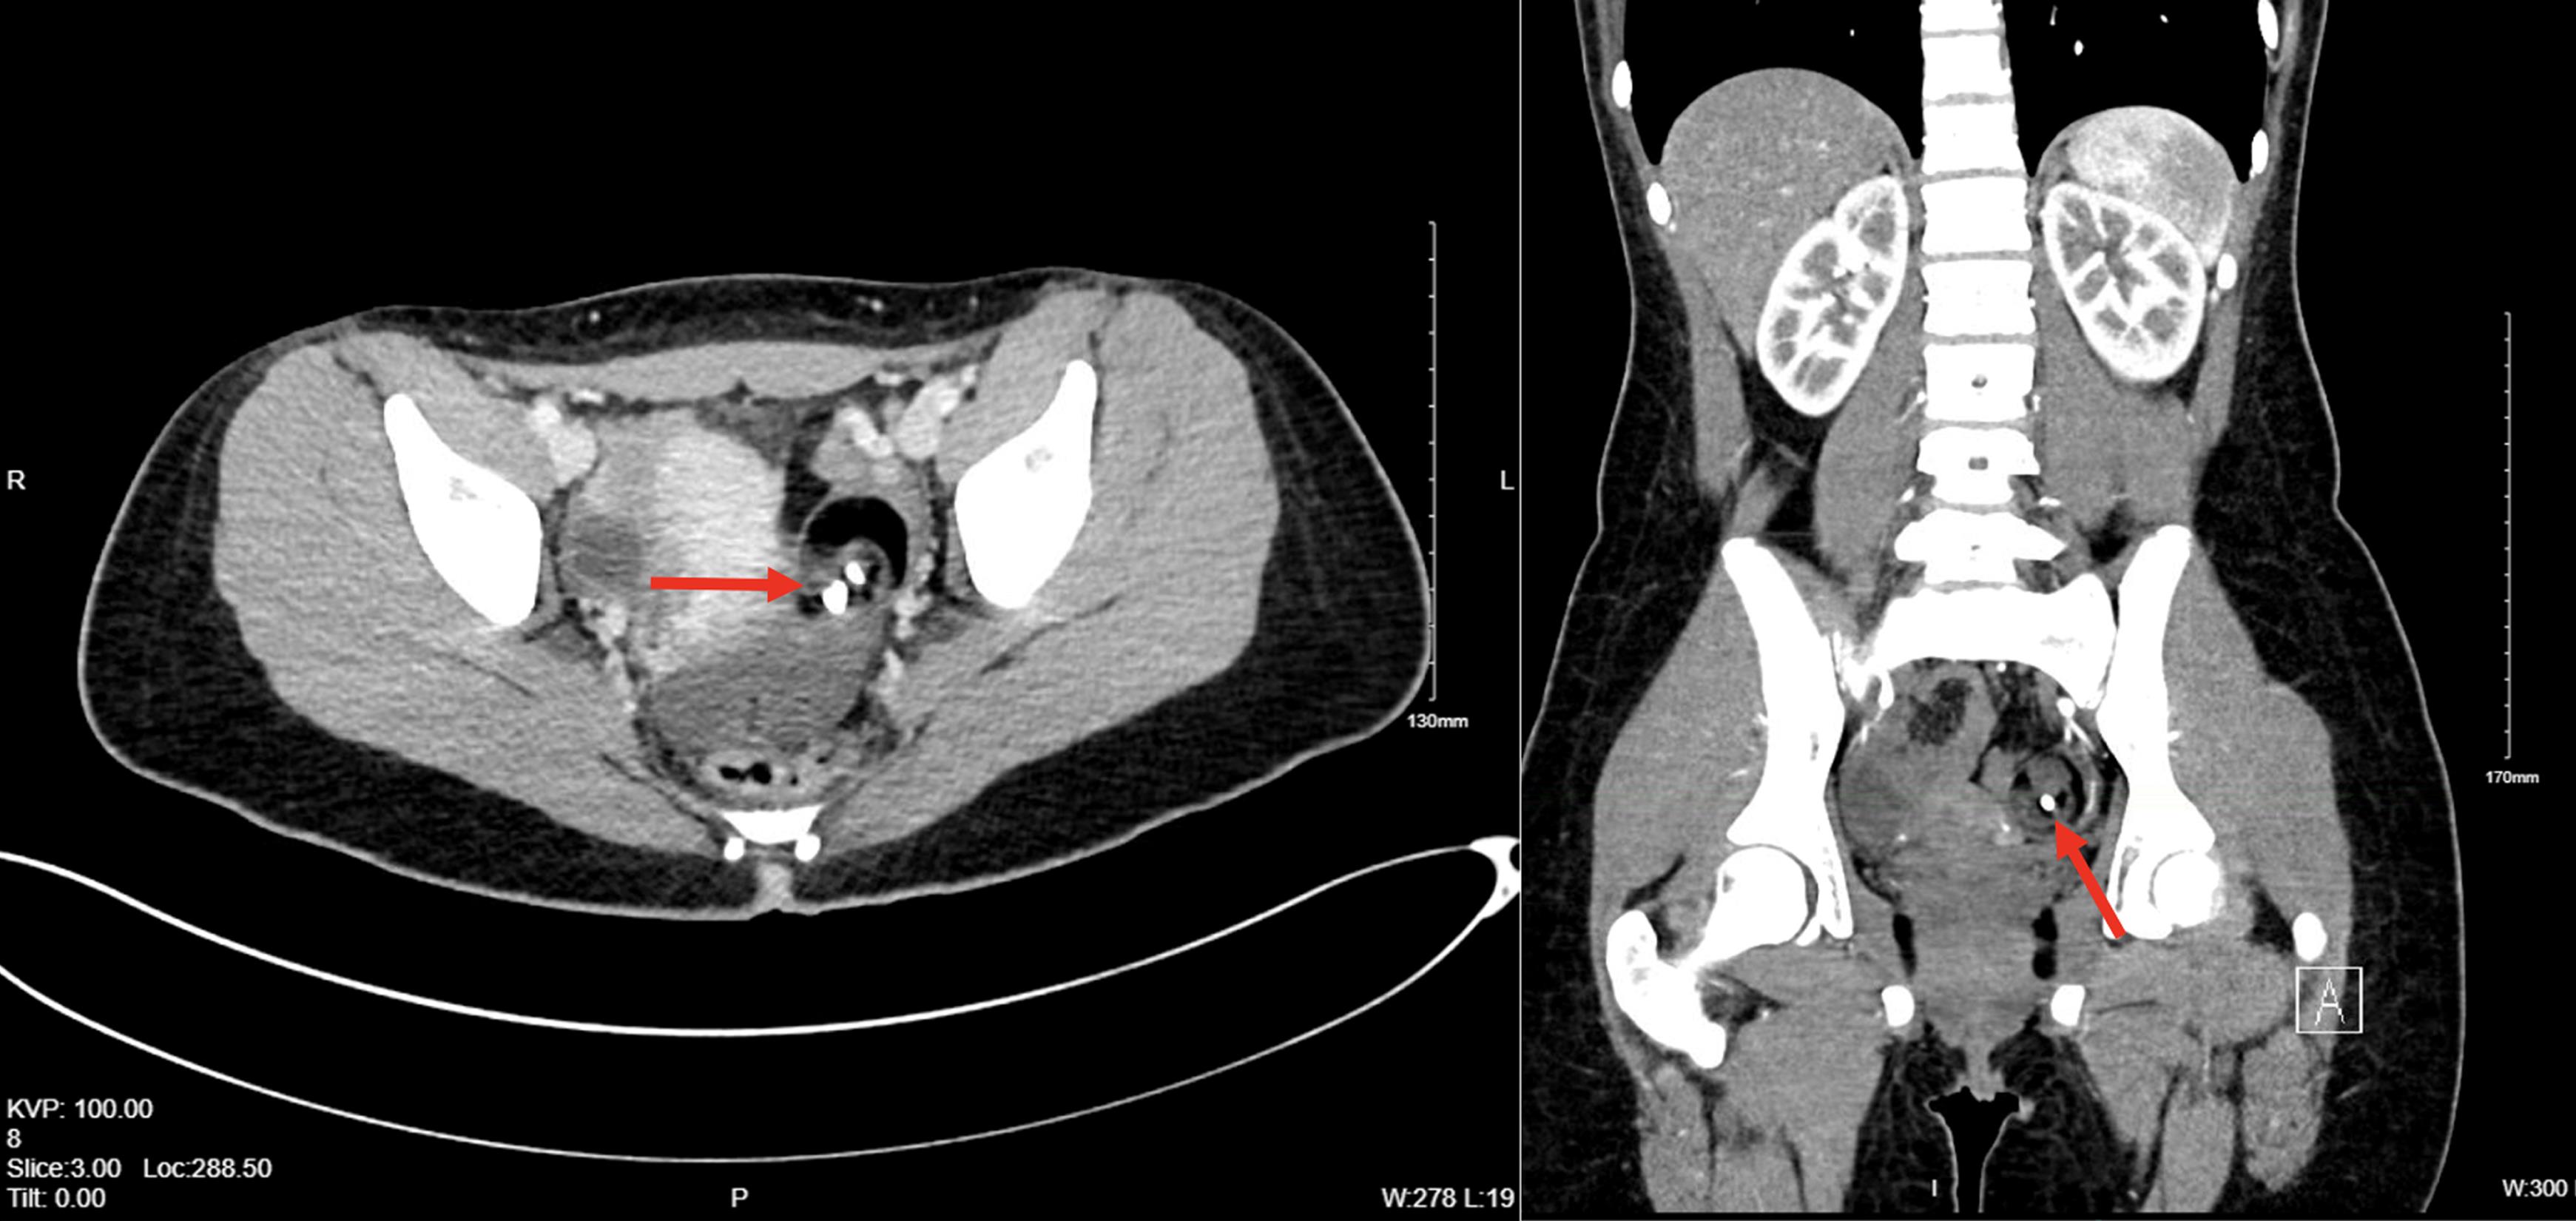

Hepatic myelopathy, a rare neurological complication of decompensated chronic liver disease, profoundly impairs quality of life. While liver transplantation represents the only curative treatment for hepatic myelopathy, we report a case in which progressive and severe spastic paraparesis was markedly improved following embolization of a paraspinal vein shunt.